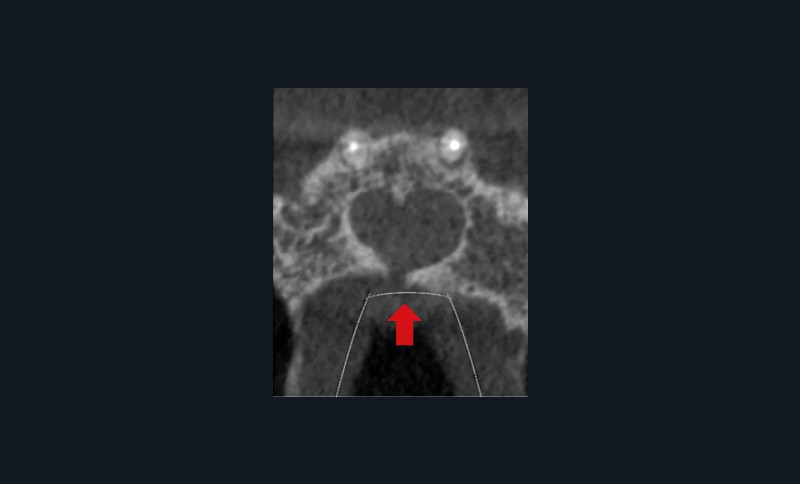

Lors de la consultation en endodontie, l’interrogatoire et l’examen clinique sont prépondérants dans l’établissement du diagnostic. Celui-ci nécessite la plupart du temps la prise de clichés radiographiques. Selon la Haute Autorité de Santé, la radiographie rétro-alvéolaire est même un prérequis obligatoire à tout traitement endodontique. Cependant, les résultats des tests cliniques, tout comme l’analyse sur radiographie rétro-alvéolaire, peuvent être subjectifs. Le CBCT pallie en partie ces limites par une analyse tridimensionnelle de l’anatomie canalaire et de ses rapports avec le milieu extra-radiculaire, permettant d’affiner le diagnostic. Il permet de détecter 60,9 % des radio-clartés péri-apicales, contre seulement 39,5 % avec une radiographie rétro-alvéolaire [2]. Cette aide au diagnostic explique pourquoi les endodontistes interrogés modifiaient leur diagnostic étiologique dans 55 % des cas présentés et leur prise en charge dans 49 % des cas lorsqu’ils avaient accès au CBCT [3]. On comprend alors qu’en cas d’incertitude ou face à une anatomie canalaire complexe, la Société Européenne d’Endodontie et l’Association Américaine d’Endodontie recommandent de réaliser un examen complémentaire 3D afin d’éviter toute perte de chance pour le patient. Cela est particulièrement pertinent pour affiner le diagnostic et retrouver une dent causale lorsque le diagnostic étiologique est compliqué (fig. 1) ainsi que pour exclure une pathologie d’origine non endodontique (fig. 2).